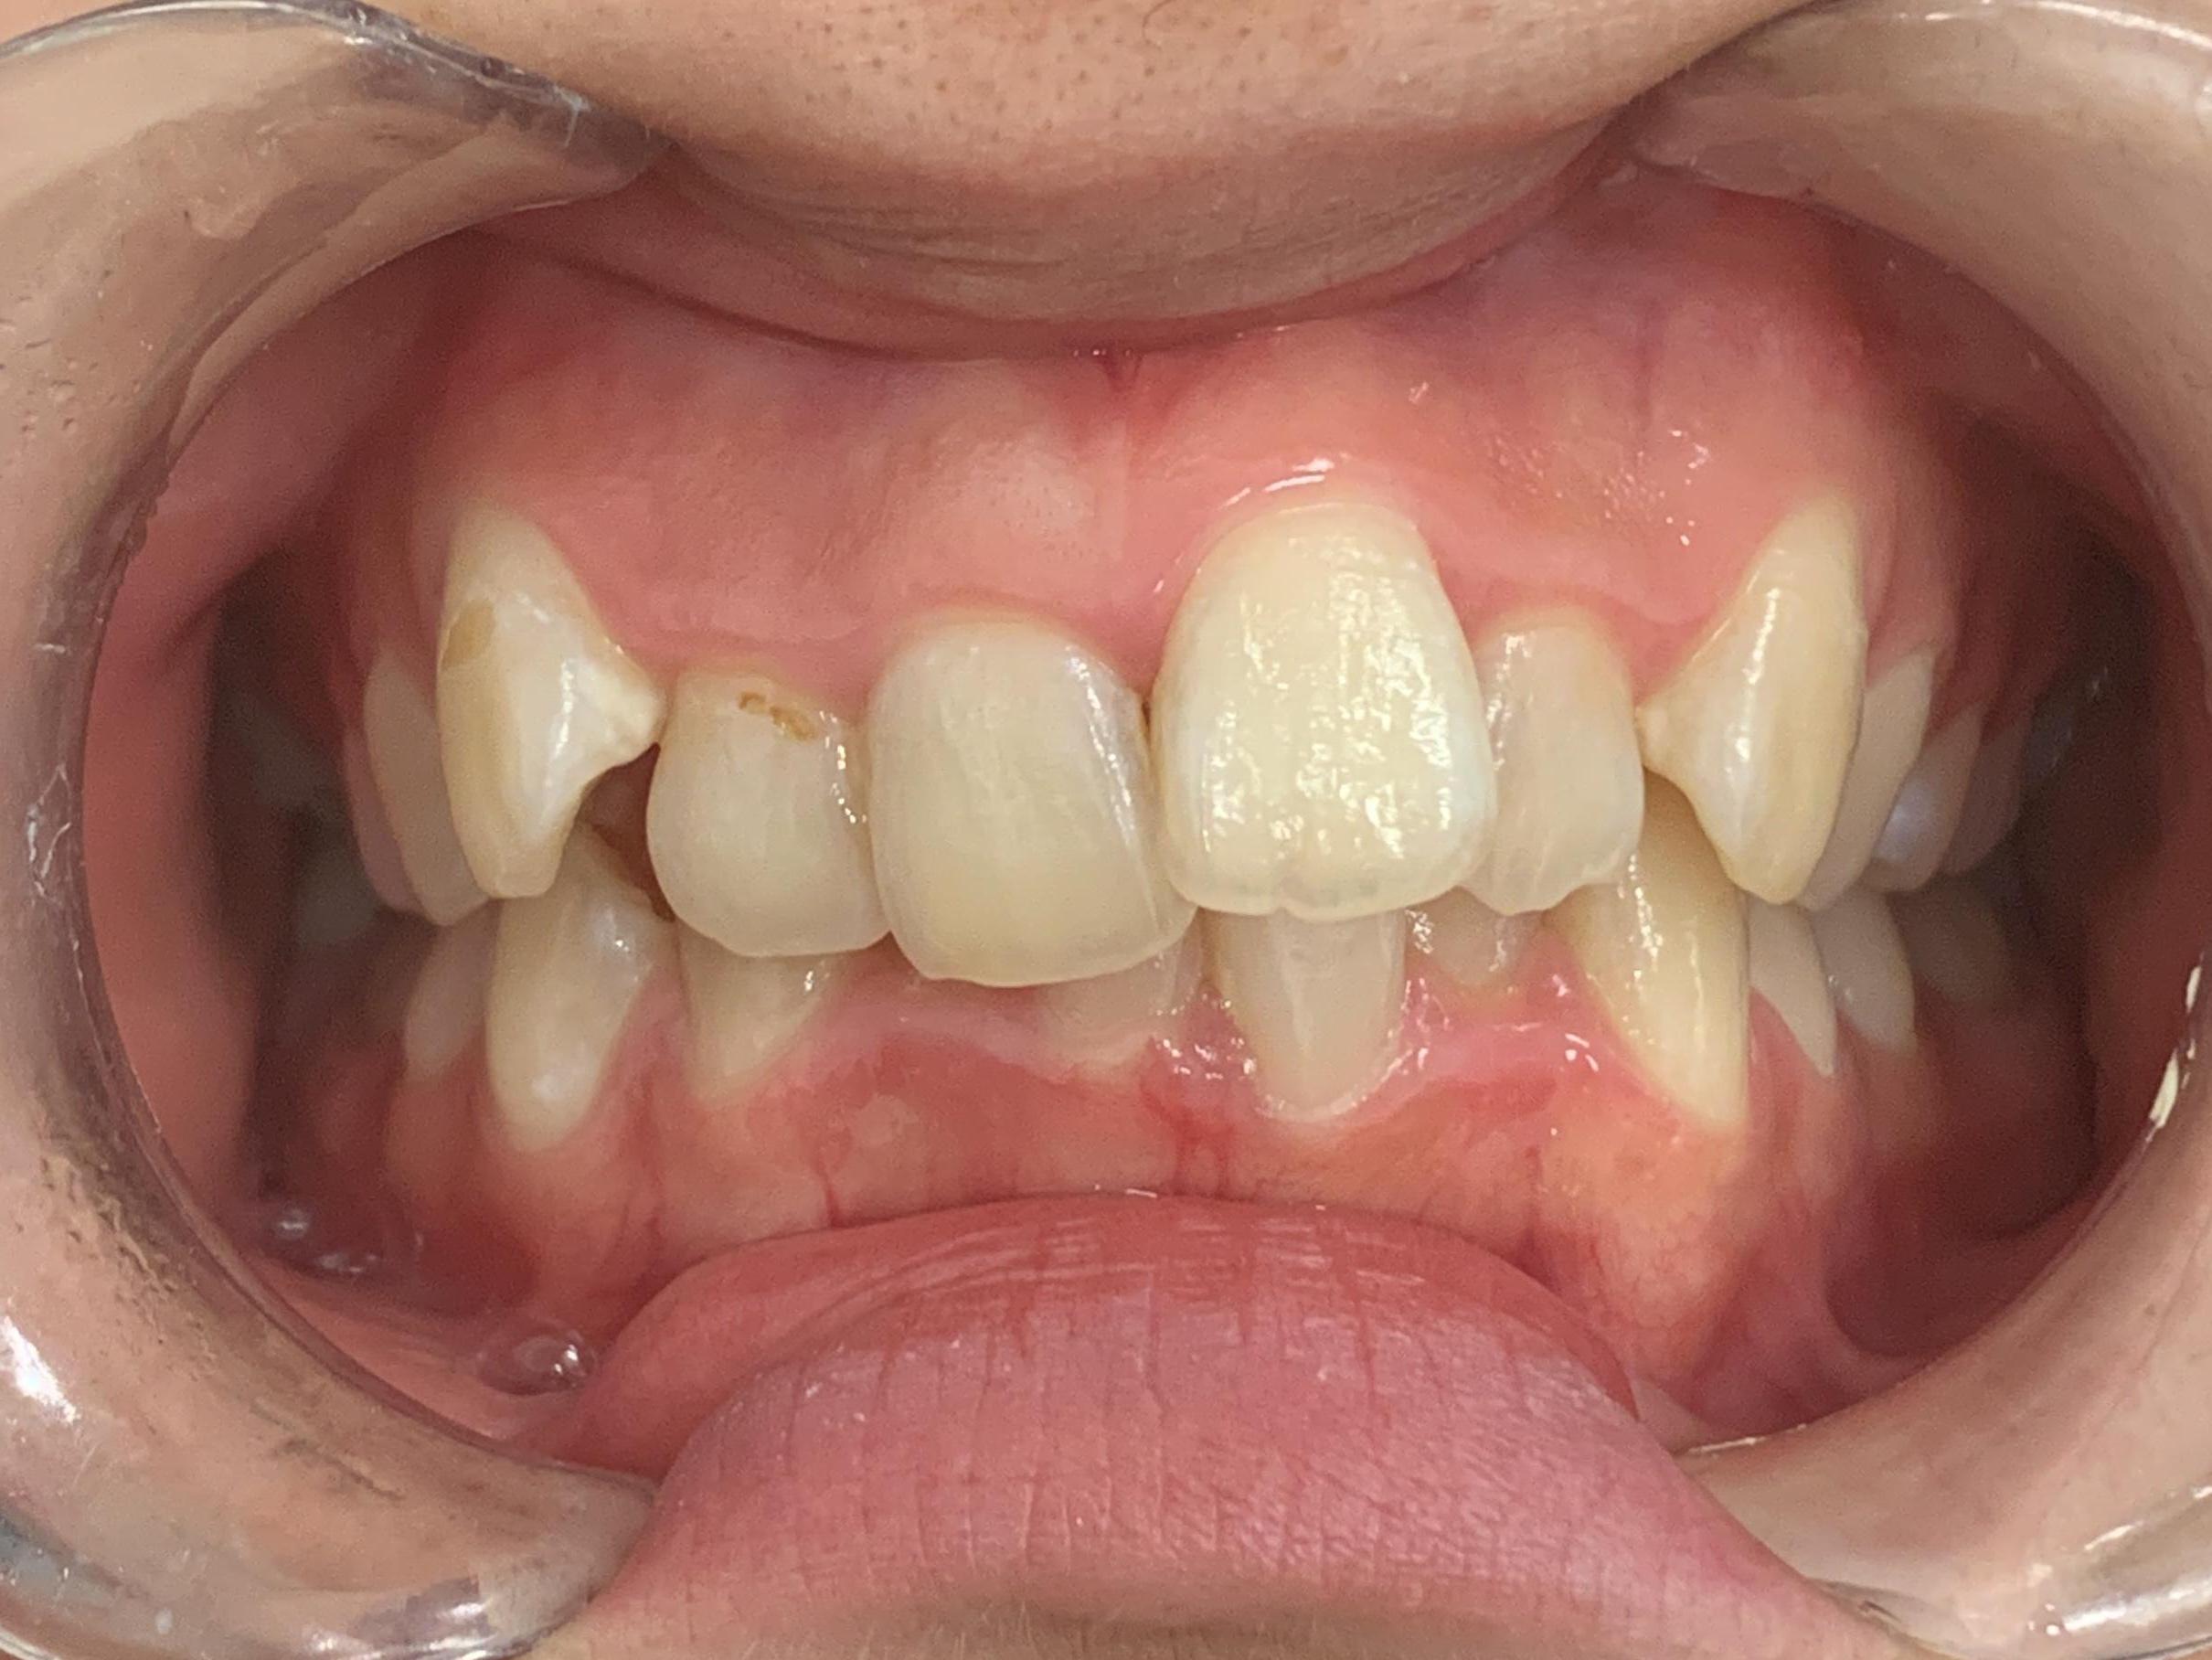

拝見すると、上下左右の前歯12本(中切歯/1番、側切歯/2番、犬歯/3番)が前後に重なり合っている「叢生(そうせい)」でした。

重なっている箇所やガタガタ具合が多いため、全体的に歯を動かしてきれいに並べることをご提案しました。